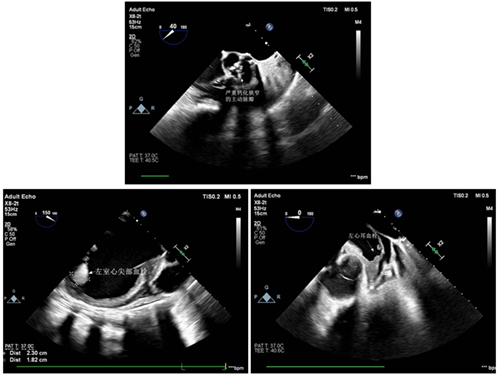

62岁的黄阿姨患重度主动脉瓣狭窄,近半年反复胸闷、憋喘、不能平卧,多次住院药物治疗,心衰始终难以纠正,生活质量极差,时刻面临着死亡的威胁。1个月前,黄阿姨到省立医院就诊,超声心动图显示LVEF仅20%,外科手术风险极高,TAVR成为最佳的手术选择。但黄阿姨左心耳及左心室存在血栓,尤其是左室心尖部的2.3*1.8cm的附壁血栓,在实施TAVR过程中一旦脱落,可能造成致命的血栓栓塞事件。心内科心衰团队为黄阿姨制定了周密的治疗方案,经过半个月的优化药物治疗,黄阿姨心功能改善得以出院,期待继续抗凝治疗后患者心腔血栓能够消失,择期入院行TAVR。